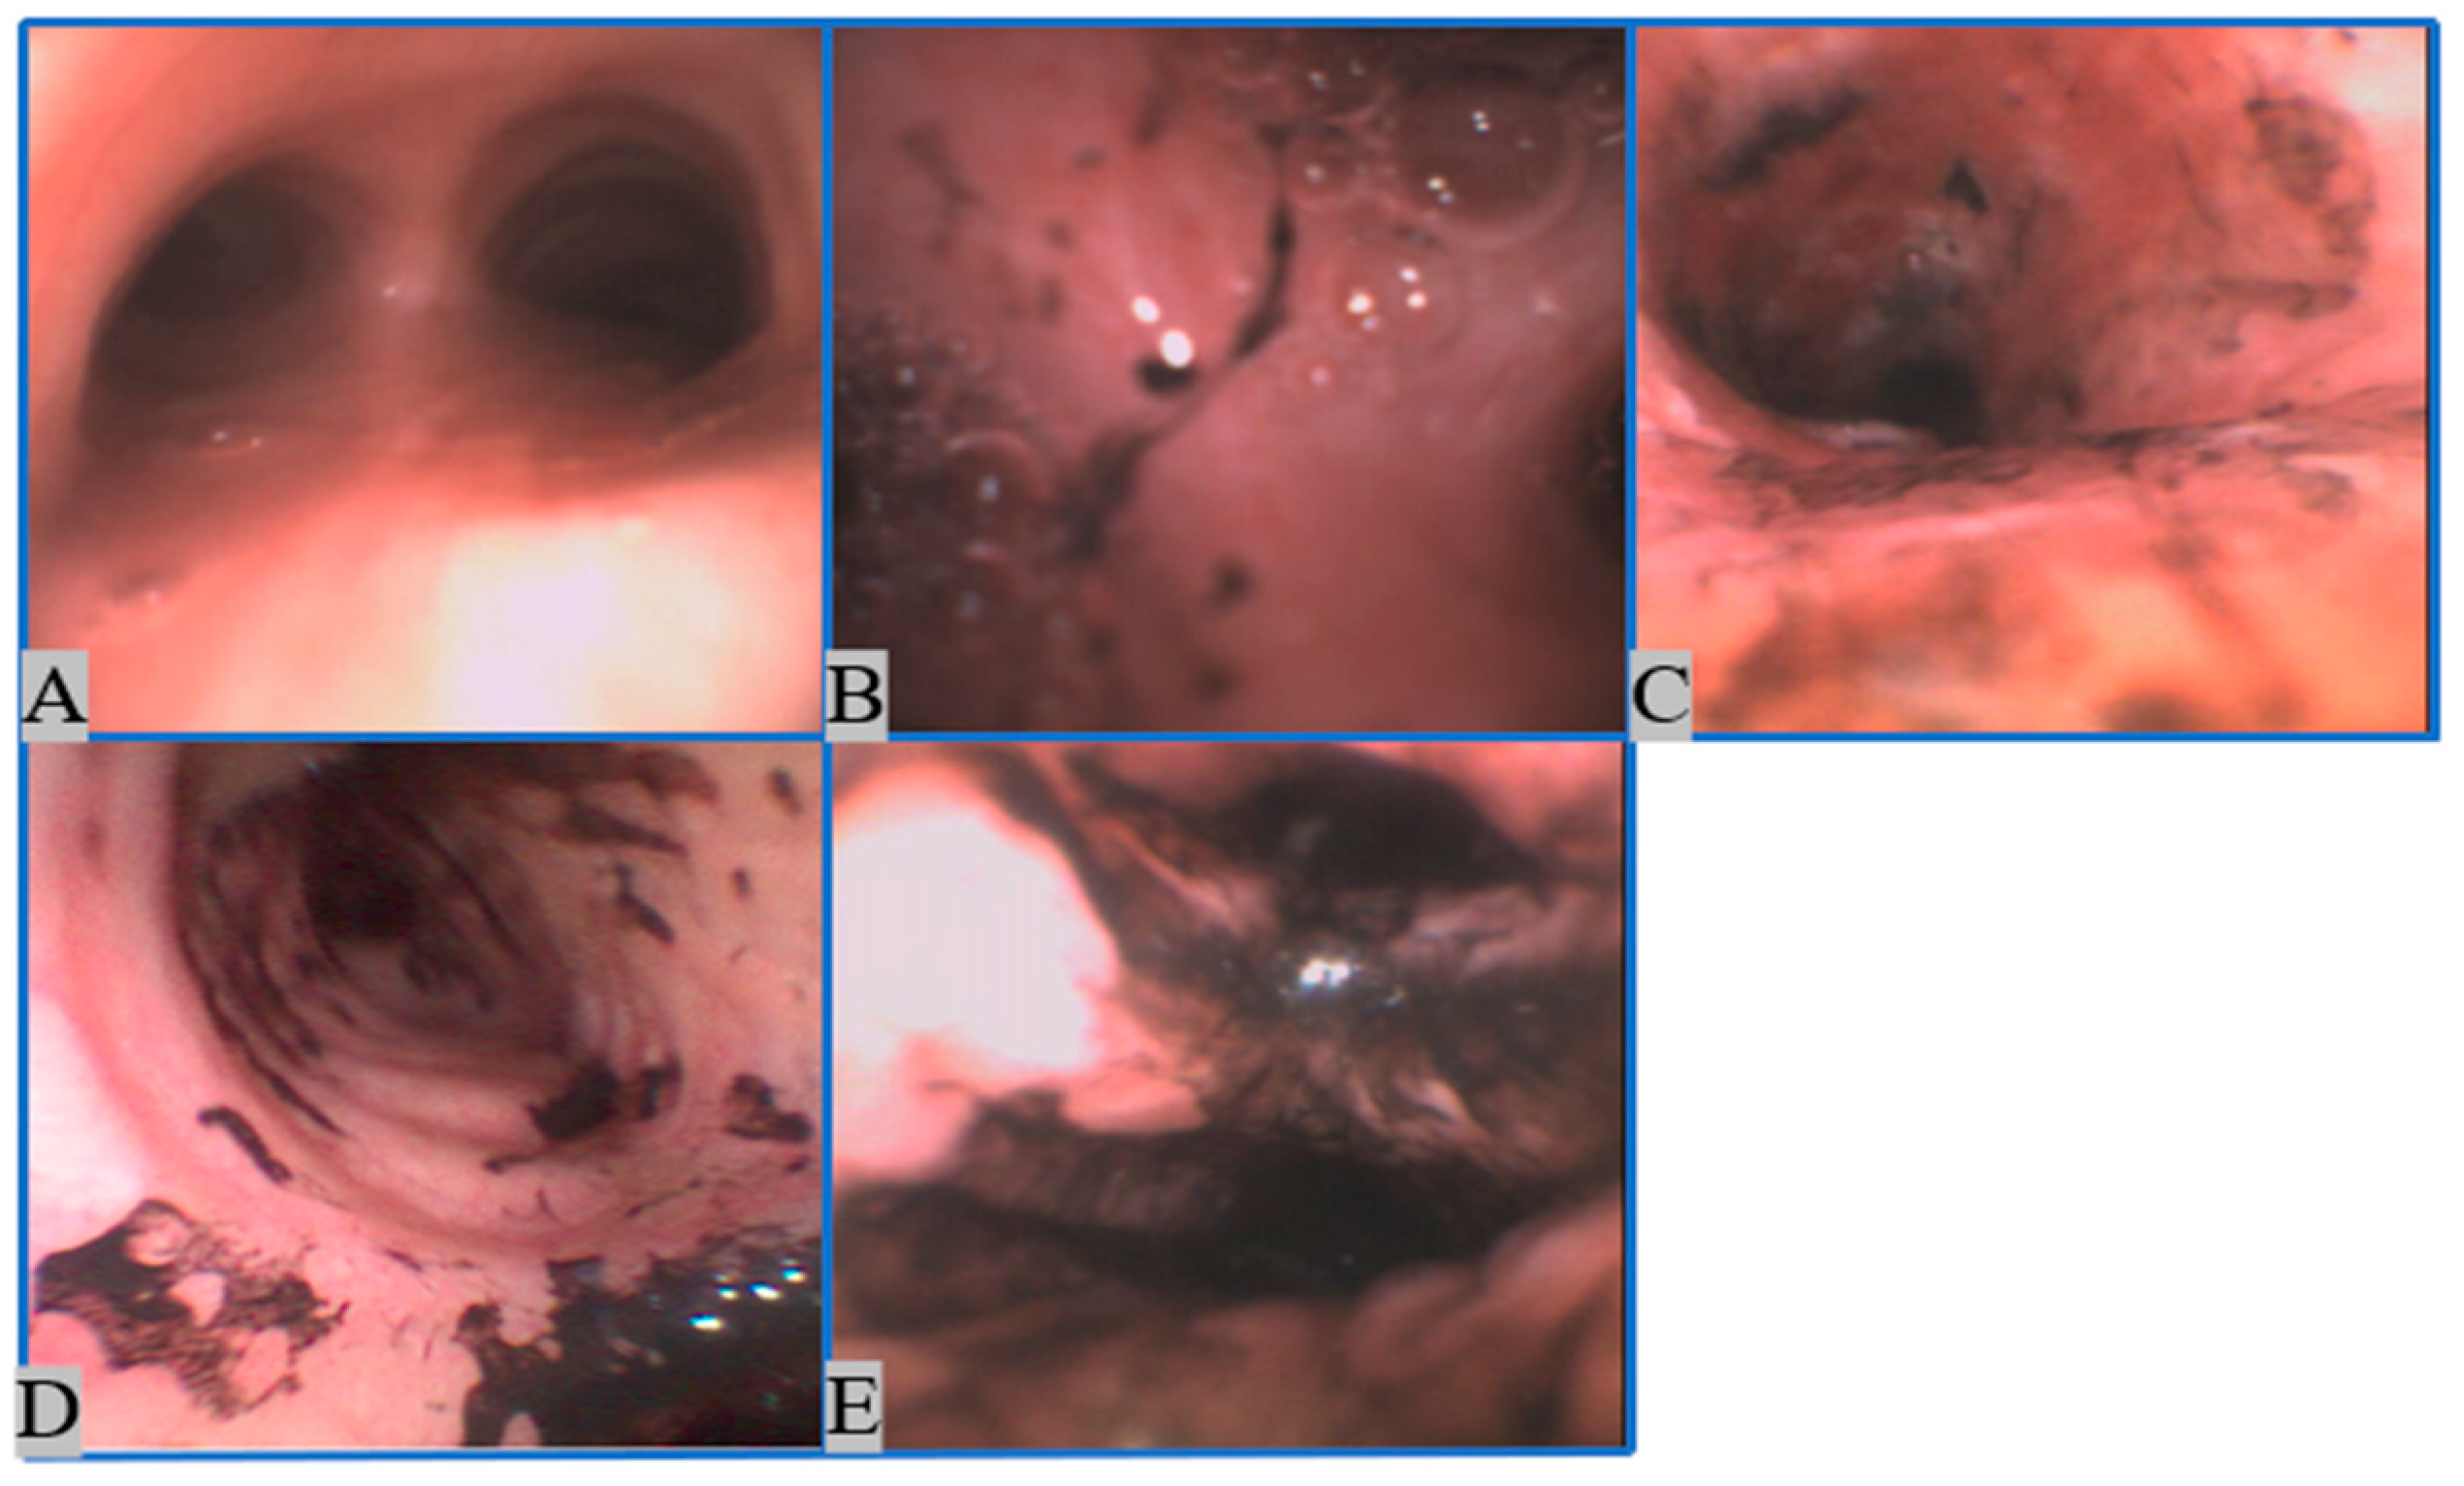

2.1.1. Image Collection